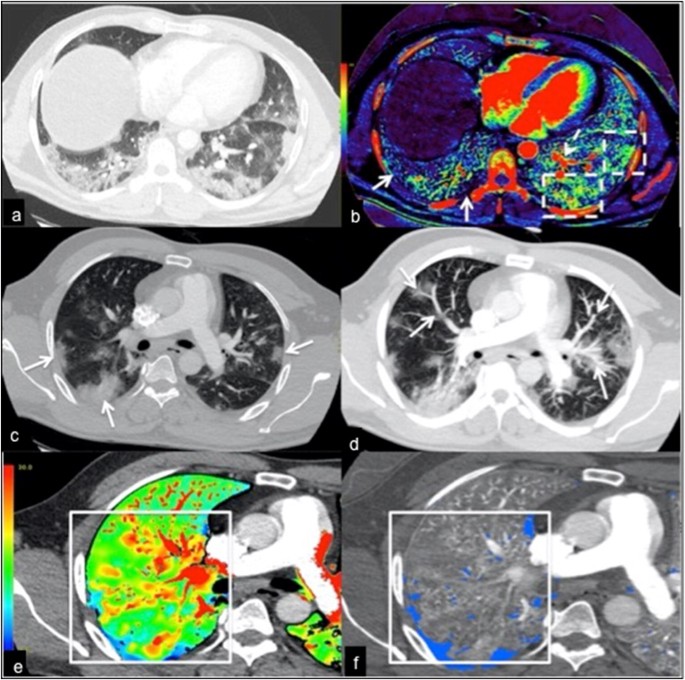

a CT pulmonary angiogram axial image at the lung base demonstrates extensive peripheral and subpleural opacities. b Corresponding iodine image shows areas of hyperperfusion in some of the opacities in the left lower lobe (dashed white boxes), while some areas show normal to reduced perfusion in some of the opacities in the right lower lobe (solid white arrows). Note also the dilated segmental pulmonary arteries in the left lower lobe (dashed white arrow). c Axial image of the upper lungs showing a few peripheral subpleural opacities (white arrows). d Axial MIP image demonstrating segmental and subsegmental vessel enlargement (white arrows). e, f Corresponding lung PBV images show subpleural areas of perfusion defects in the right lung, which are associated with areas of increased perfusion proximally (white boxes). No pulmonary embolism was identified